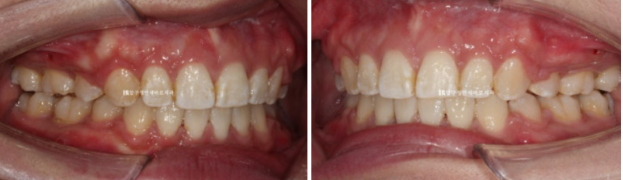

23.02~24.09

전 후 정면 스마일 사진입니다.

좌우 입꼬리 안쪽에 원래 없던 입동굴이 생겼습니다.

너무 크지 않은 적절한 입동굴은 미소심미에 중요합니다.

또 한가지, 미소심미에서 빼놓을 수 없는 것은 스마일라인입니다.

스마일라인은 윗니 끝단을 이은 선을 말합니다.

이것이 아랫입술과 평행해야 웃을 때 아름답습니다.

아랫입술에 비하여 너무 편평해서 일자였던 스마일라인이 아랫입술에 평행하게 동그란 모양으로 바뀌었습니다.

입술부전증이 해결되어 이제 입술에 힘을 빼도 자연스럽게 다물어집니다.